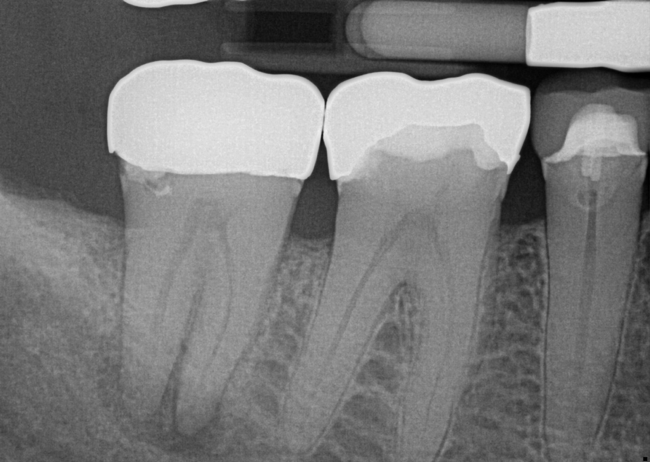

Fig 3. Preoperative maxillary left bicuspid.

Figure 3

The patient presented with temperature sensitivity and pain during mastication (Figure 3). Local anesthesia was delivered, and steps 1 through 4 were performed.